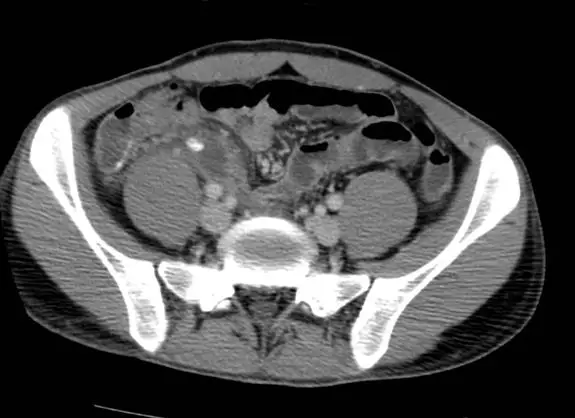

20 歲男性因急性腹痛、⾼燒求診,接受對比劑注射後之電腦斷層掃描檢查如圖,最可能之診斷為何?

本題圖片為骨盆腔軸切面(axial view)的腹部對比劑注射後 CT 影像,可見:

- 位置:右下腹(右髂窩區域)可見一管狀、擴張的盲管結構

- 管徑增大:闌尾直徑明顯 >6 mm(正常 <6 mm),呈現異常擴張

- 管壁增厚且強化:對比劑注射後管壁有明顯環狀強化(rim enhancement),符合發炎反應

- 周圍脂肪絞攣(periappendiceal fat stranding):闌尾周圍脂肪密度增加、呈條索狀混濁,代表局部炎症蔓延

- 管腔內液體:管腔內含液體,提示阻塞後積液

- 無明顯游離氣體:無穿孔後氣腹徵象

- 腸系膜淋巴結:周圍可見數個淋巴結,反應性腫大

影像判讀意義:右下腹擴張的盲管狀結構(直徑 >6 mm)合併管壁強化與周圍脂肪絞攣,是急性闌尾炎的典型 CT 三聯徵(triad),CT 診斷急性闌尾炎的敏感度達 95%、特異度 94%。